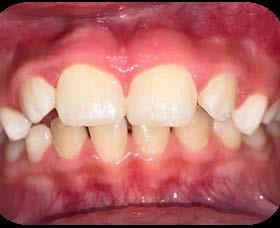

Entre los elementos que conforman al sistema estomatognático, están los dientes caninos, órganos dentales esenciales en la fisiología masticatoria; punto de unión y continuidad estética entre la línea de la sonrisa y el corredor posterior del arco dental, además de que ejercen la función de pilares estabilizadores en la oclusión fisiológica (Figura 1).

Los caninos son indispensables durante los movimientos de lateralidad y vitales para la continuidad de los arcos dentales, tanto en la dentición decidua como en la permanente; son responsables del funcionamiento y la armonía oclusal. Su posición adecuada en el arco asegura un buen contorno de la cara, sonrisa agradable y armónica con la estética facial. (Figura 2).

El canino divide su cara vestibular en 2 vertientes, una mesial que se continúa con los incisivos y otra distal que se alinea con los dientes posteriores, razón por la cual su ausencia genera alteraciones muy importantes en la oclusión y la estabilidad fisiológica del sistema estomatognático (Figura 3).